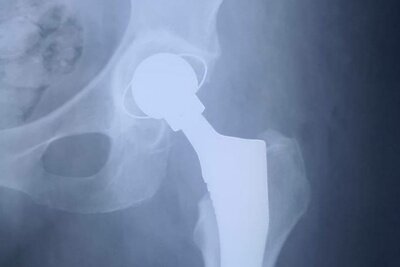

Рентгеновский снимок жительницы Луховиц после эндопротезирования тазобедренных суставов © Сайт Министерства здравоохранения Московской области

РИАМО - 19 сен. В Луховицкой больнице благодаря расширению возможности оказания высокотехнологичной медицинской помощи теперь выполняют операции по тотальному эндопротезированию тазобедренных суставов, первую из них уже провели 68-летней пациентке, сообщает пресс-служба министерства здравоохранения Московской области.

Женщина поступила в травматологическое отделение Луховицкой больницы. Медики выявили у нее перелом шейки бедренной кости со смещением. Травму жительница получила при падении дома.

Врач-травматолог Луховицкой больницы Андрей Королев рассказал, что врачи провели обследование и приняли решение о проведении тотального эндопротезирования левого тазобедренного сустава.

«Операция прошла успешно и уже через 2 дня пациентка могла самостоятельно садиться на кровати и свешивать ноги. На третьи сутки после хирургического вмешательства начался послеоперационный восстановительный этап лечения - пациентка начала ходить с инструктором ЛФК с помощью ходунков. Такие виды хирургической помощи стали доступны в нашей больнице после получения лицензии и оснащения современным оборудованием», - добавил Королев.